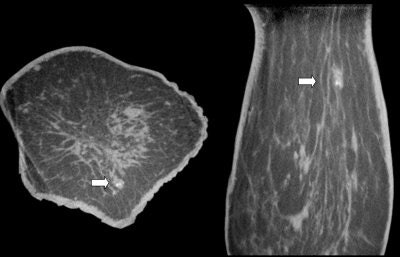

![]() |

| A 7-mm cluster of suspicious microcalcifications. Coronal and axial breast CT scans show microcalcifications in an ill-defined mass (DCIS). Image courtesy of John Boone, Ph.D. |